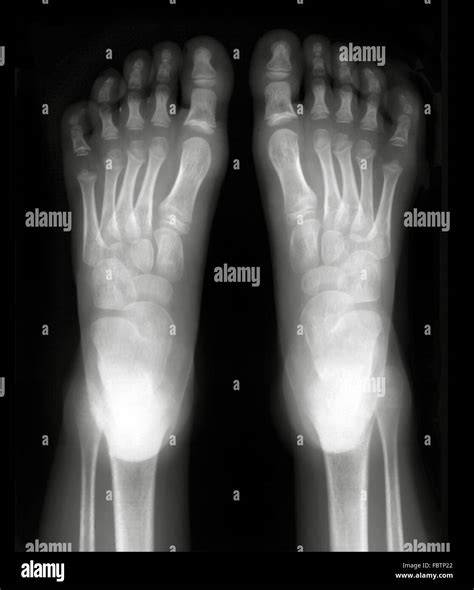

A Normal Foot Xray is a radiographic image of the foot that shows the bones, joints, and soft tissues in detail. This imaging technique uses X-rays to create pictures of the internal structures of the foot, allowing healthcare providers to diagnose fractures, dislocations, arthritis, and other abnormalities. The term “normal” refers to an Xray that does not show any significant abnormalities or pathologies, indicating that the foot’s structure is intact and healthy.

In a normal Xray, the bones should appear smooth and continuous, with no visible fractures or dislocations. The joint spaces should be uniform, and there should be no signs of bone spurs or other abnormalities.

In summary, a Normal Foot Xray is an essential diagnostic tool that provides valuable insights into the structure and health of the foot. By understanding the indications, preparation, procedure, and interpretation of a Normal Foot Xray, healthcare professionals and patients can work together to ensure accurate diagnoses and effective treatment plans. Whether used for routine check-ups or to assess specific concerns, a Normal Foot Xray plays a crucial role in maintaining foot health and overall well-being.